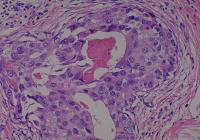

Figure-1: An example of Infiltrating duct carcinoma of breas tissue. For listing of organs in this slide, please click on Slide Info.